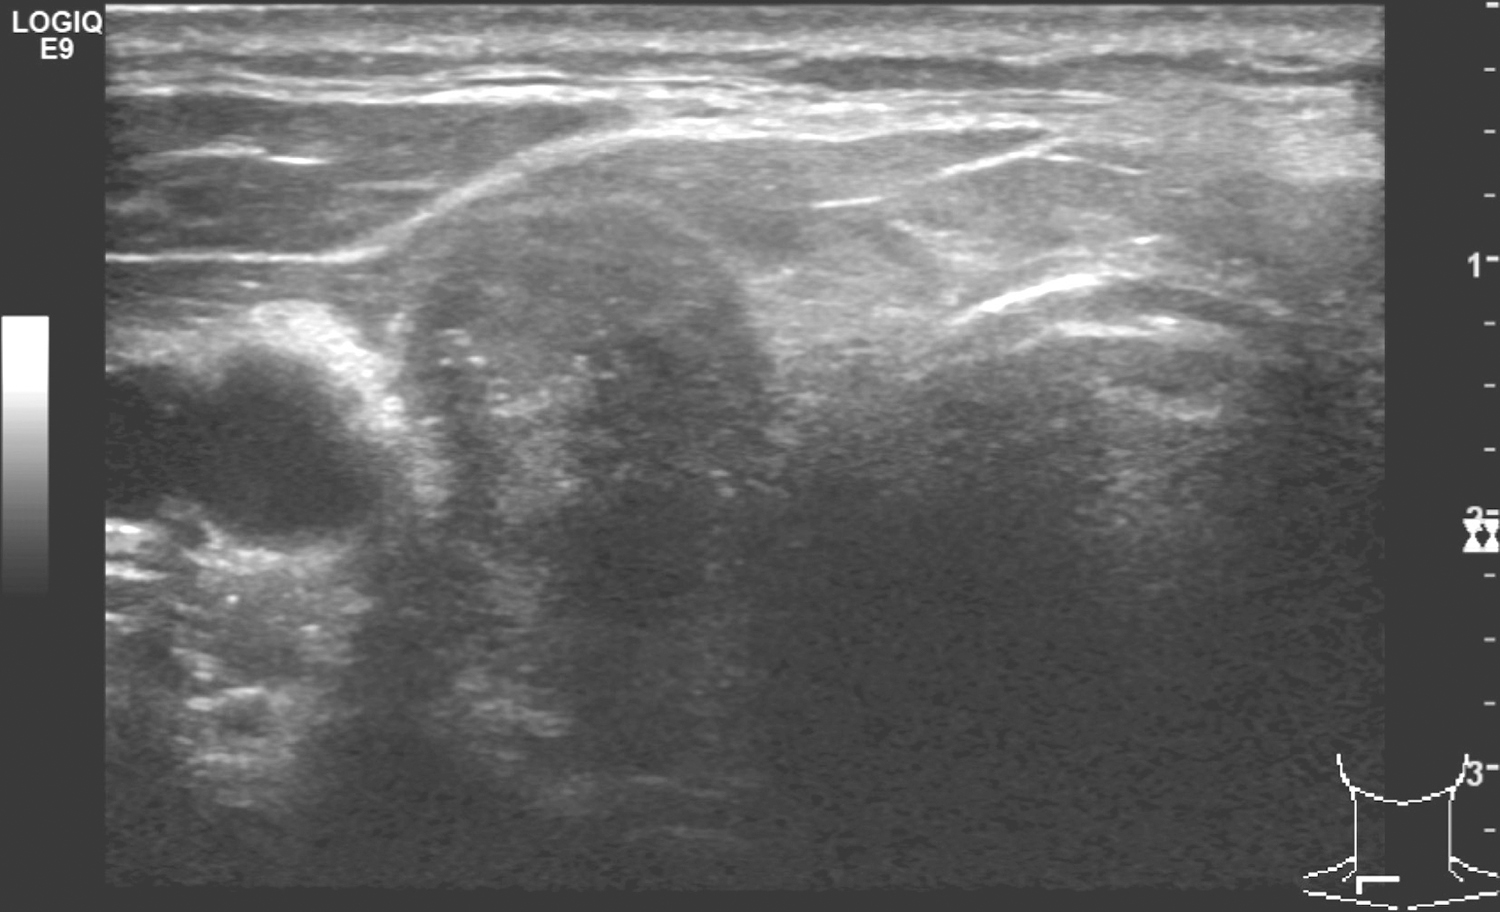

1.2013年10月9日,颈部超声右侧甲状腺上极有低回声病变,约1.6cm×1.8cm,边界不清(图1)。左叶上极有低回声病变,约0.7cm×1.1cm,边界不清(图2)。右颈Ⅱ、Ⅲ、Ⅳ、Ⅵ、Ⅶ区及左颈Ⅳ、Ⅵ区多发低回声结节,大者约1.3cm,位于右侧气管食管沟。

图1 颈部超声示右侧甲状腺上极低回声病变

超声诊断:双侧甲状腺上极实性病变,恶性;双颈(范围如上)多发淋巴结转移瘤。